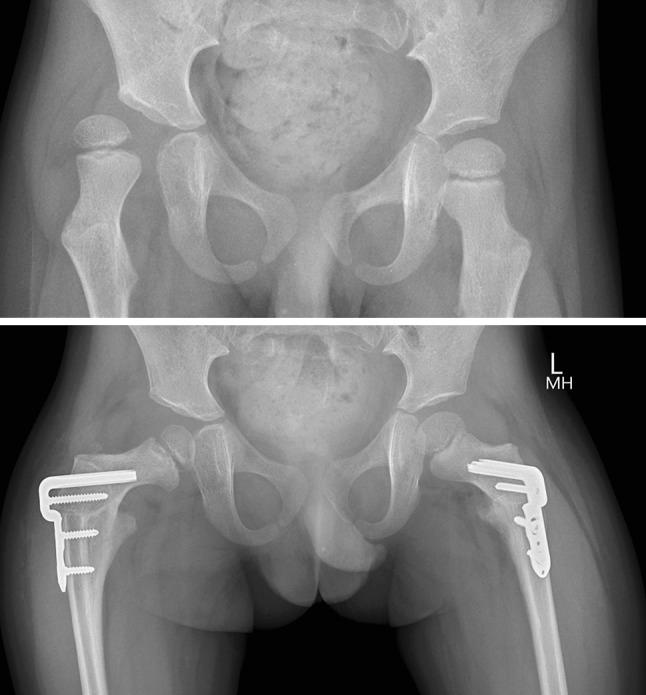

Proximal femoral osteotomy is the most common major reconstructive surgery in the region of the hip joint in children and adolescents. Given that it may be required across a wide range of ages and indications, appropriate instrumentation is necessary to ensure a technically satisfactory result. Recent developments in fixation include cannulation of the blade plate and locking screw technology.

We conducted a prospective audit of our first 25 patients who had a unilateral or bilateral proximal femoral osteotomy using a recently available system which combines cannulation and locking plate technology. The principal outcome measures were the radiographic position of the osteotomy at the time of union and surgical adverse events.

Forty-five proximal femoral osteotomies were performed in 25 patients, mean age 8 years (range 3-17 years), for a variety of indications, the most common of which was hip subluxation in children with cerebral palsy. All osteotomies were soundly united by 6 weeks in children and by 3 months in adolescents, in the position achieved intra-operatively. There were no revision procedures and the technical goals of surgery were achieved in all patients. There was one adverse event, a low-grade peri-prosthetic infection, diagnosed at the time of implant removal.

In this prospective audit of our first 25 patients, the new system performed well across a wide range of ages, body weights and surgical indications. Further comparative studies will be required to determine whether it offers additional advantages over more traditional systems.